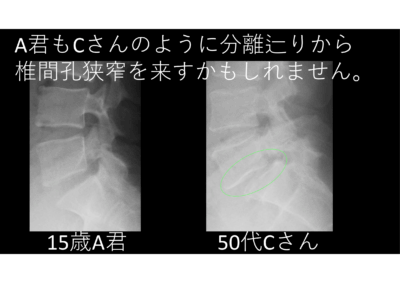

だから何とか安静と硬性コルセットで引っ付いてくれ! 2025年11月、12月の分離症例 A君、15歳の男の子、見るからに運動神経の塊みたいな明るい子。分離症判明…